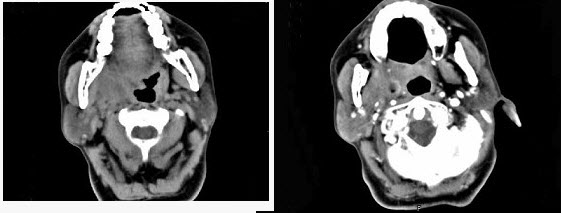

14、单项选择题

女,4岁,右侧颈部可扪及一包块约两个月,无热无痛,CT如图所示,最可能的诊断为()。

A.咽旁血管外皮瘤

B.咽旁副神经节瘤

C.咽旁脓肿

D.咽旁神经纤维瘤

E.咽旁小唾液腺混合瘤